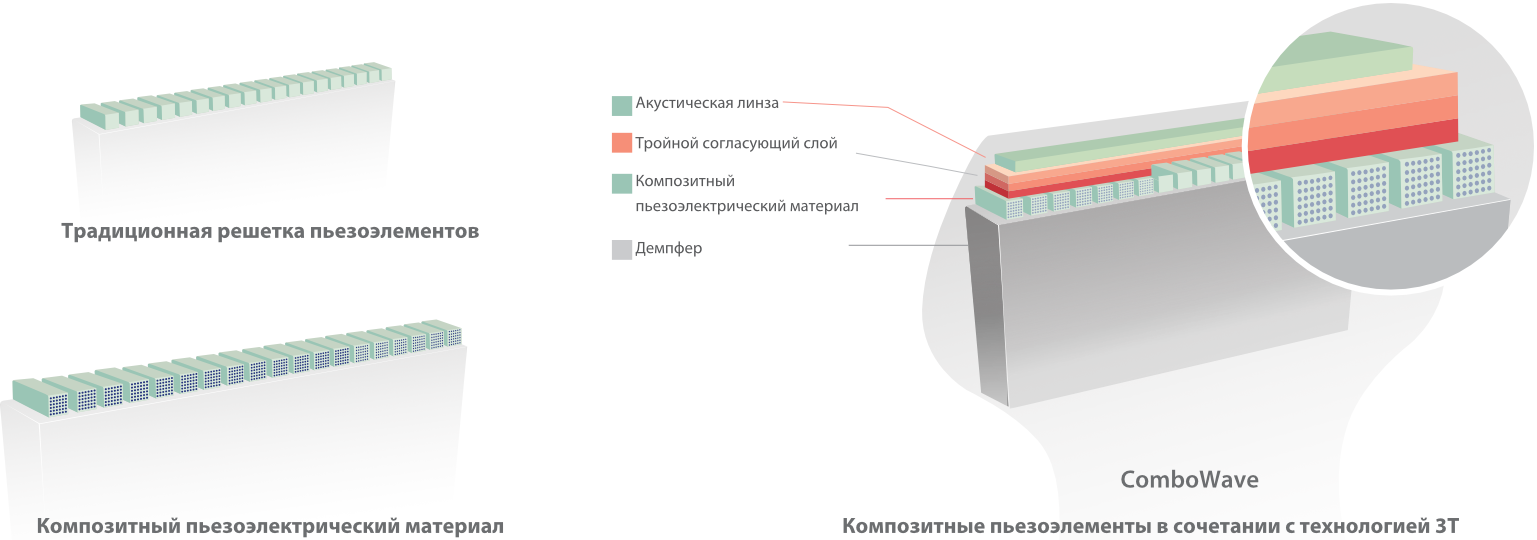

–£―΄―¹–Ψ–Κ–Ψ–Κ–Α―΅–Β―¹―²–≤–Β–Ϋ–Ϋ–Α―è ―²–Β―Ö–Ϋ–Ψ–Μ–Ψ–≥–Η―è –Η–Ζ–≥–Ψ―²–Ψ–≤–Μ–Β–Ϋ–Η―è –¥–Α―²―΅–Η–Κ–Ψ–≤

–£–Ϋ–Β–¥―Ä–Β–Ϋ–Η–Β –≤ DC-80 EXP –¥–Α―²―΅–Η–Κ–Ψ–≤ ―¹–≤–Β―Ä―Ö–≤―΄―¹–Ψ–Κ–Ψ–Ι –Ω―Ä–Ψ–Η–Ζ–≤–Ψ–¥–Η―²–Β–Μ―¨–Ϋ–Ψ―¹―²–Η –Ψ–±–Β―¹–Ω–Β―΅–Η–≤–Α–Β―² –¥–Μ―è –£–Α―¹ –Ω―Ä–Β–≤–Ψ―¹―Ö–Ψ–¥–Ϋ–Ψ–Β –Κ–Α―΅–Β―¹―²–≤–Ψ –≤–Η–Ζ―É–Α–Μ–Η–Ζ–Α―Ü–Η–Η.

–€–Ψ–Ϋ–Ψ–Κ―Ä–Η―¹―²–Α–Μ–Μ–Η―΅–Β―¹–Κ–Η–Β –¥–Α―²―΅–Η–Κ–Η ―¹ ―²–Β―Ö–Ϋ–Ψ–Μ–Ψ–≥–Η–Β–Ι 3–Δ?

–ë–Μ–Α–≥–Ψ–¥–Α―Ä―è ―¹–Ψ―΅–Β―²–Α–Ϋ–Η―é ―²–Β―Ö–Ϋ–Ψ–Μ–Ψ–≥–Η–Η 3–Δ? (–Δ―Ä–Ψ–Ι–Ϋ–Ψ–Ι ―¹–Ψ–≥–Μ–Α―¹―É―é―â–Η–Ι ―¹–Μ–Ψ–Ι, ―²–Β―Ö–Ϋ–Ψ–Μ–Ψ–≥–Η―è –Ω–Ψ–Μ–Ϋ–Ψ―¹―²―¨―é ―Ä–Α–Ζ–¥–Β–Μ–Β–Ϋ–Ϋ―΄―Ö –Κ―Ä–Η―¹―²–Α–Μ–Μ–Ψ–≤, ―²–Β―Ä–Φ–Ψ–Κ–Ψ–Ϋ―²―Ä–Ψ–Μ―¨ –Α–Κ―É―¹―²–Η―΅–Β―¹–Κ–Ψ–Ι –Μ–Η–Ϋ–Ζ―΄) –Η –Φ–Ψ–Ϋ–Ψ–Κ―Ä–Η―¹―²–Α–Μ–Μ–Η―΅–Β―¹–Κ–Η―Ö –¥–Α―²―΅–Η–Κ–Ψ–≤ –Ψ–±–Β―¹–Ω–Β―΅–Η–≤–Α–Β―²―¹―è –Κ–Α–Κ –±–Ψ–Μ–Β–Β –≤―΄―¹–Ψ–Κ–Α―è ―Ä–Α–Ζ―Ä–Β―à–Α―é―â–Α―è, ―²–Α–Κ –Η –Ω―Ä–Ψ–Ϋ–Η–Κ–Α―é―â–Α―è ―¹–Ω–Ψ―¹–Ψ–±–Ϋ–Ψ―¹―²―¨, –≤ ―Ä–Β–Ζ―É–Μ―¨―²–Α―²–Β ―΅–Β–≥–Ψ ―Ä–Β―à–Α–Β―²―¹―è –Ω―Ä–Ψ–±–Μ–Β–Φ–Α –Η―¹―¹–Μ–Β–¥–Ψ–≤–Α–Ϋ–Η–Ι ―²–Β―Ö–Ϋ–Η―΅–Β―¹–Κ–Η ―¹–Μ–Ψ–Ε–Ϋ―΄―Ö –Ω–Α―Ü–Η–Β–Ϋ―²–Ψ–≤.